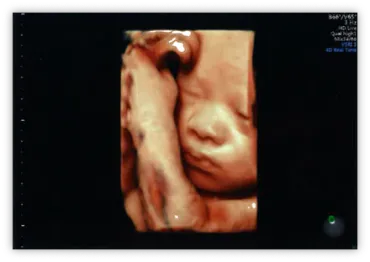

4Dエコーは、赤ちゃんの顔立ちや仕草を観察できるため、親子の絆を深め、喜びを分かち合う機会を提供します。

赤ちゃんの顔や仕草が見え、親子の絆を深めます。

4D超音波検査では、お腹の赤ちゃんの立体動画を撮影でき、赤ちゃんの様々な仕草を観察できます。